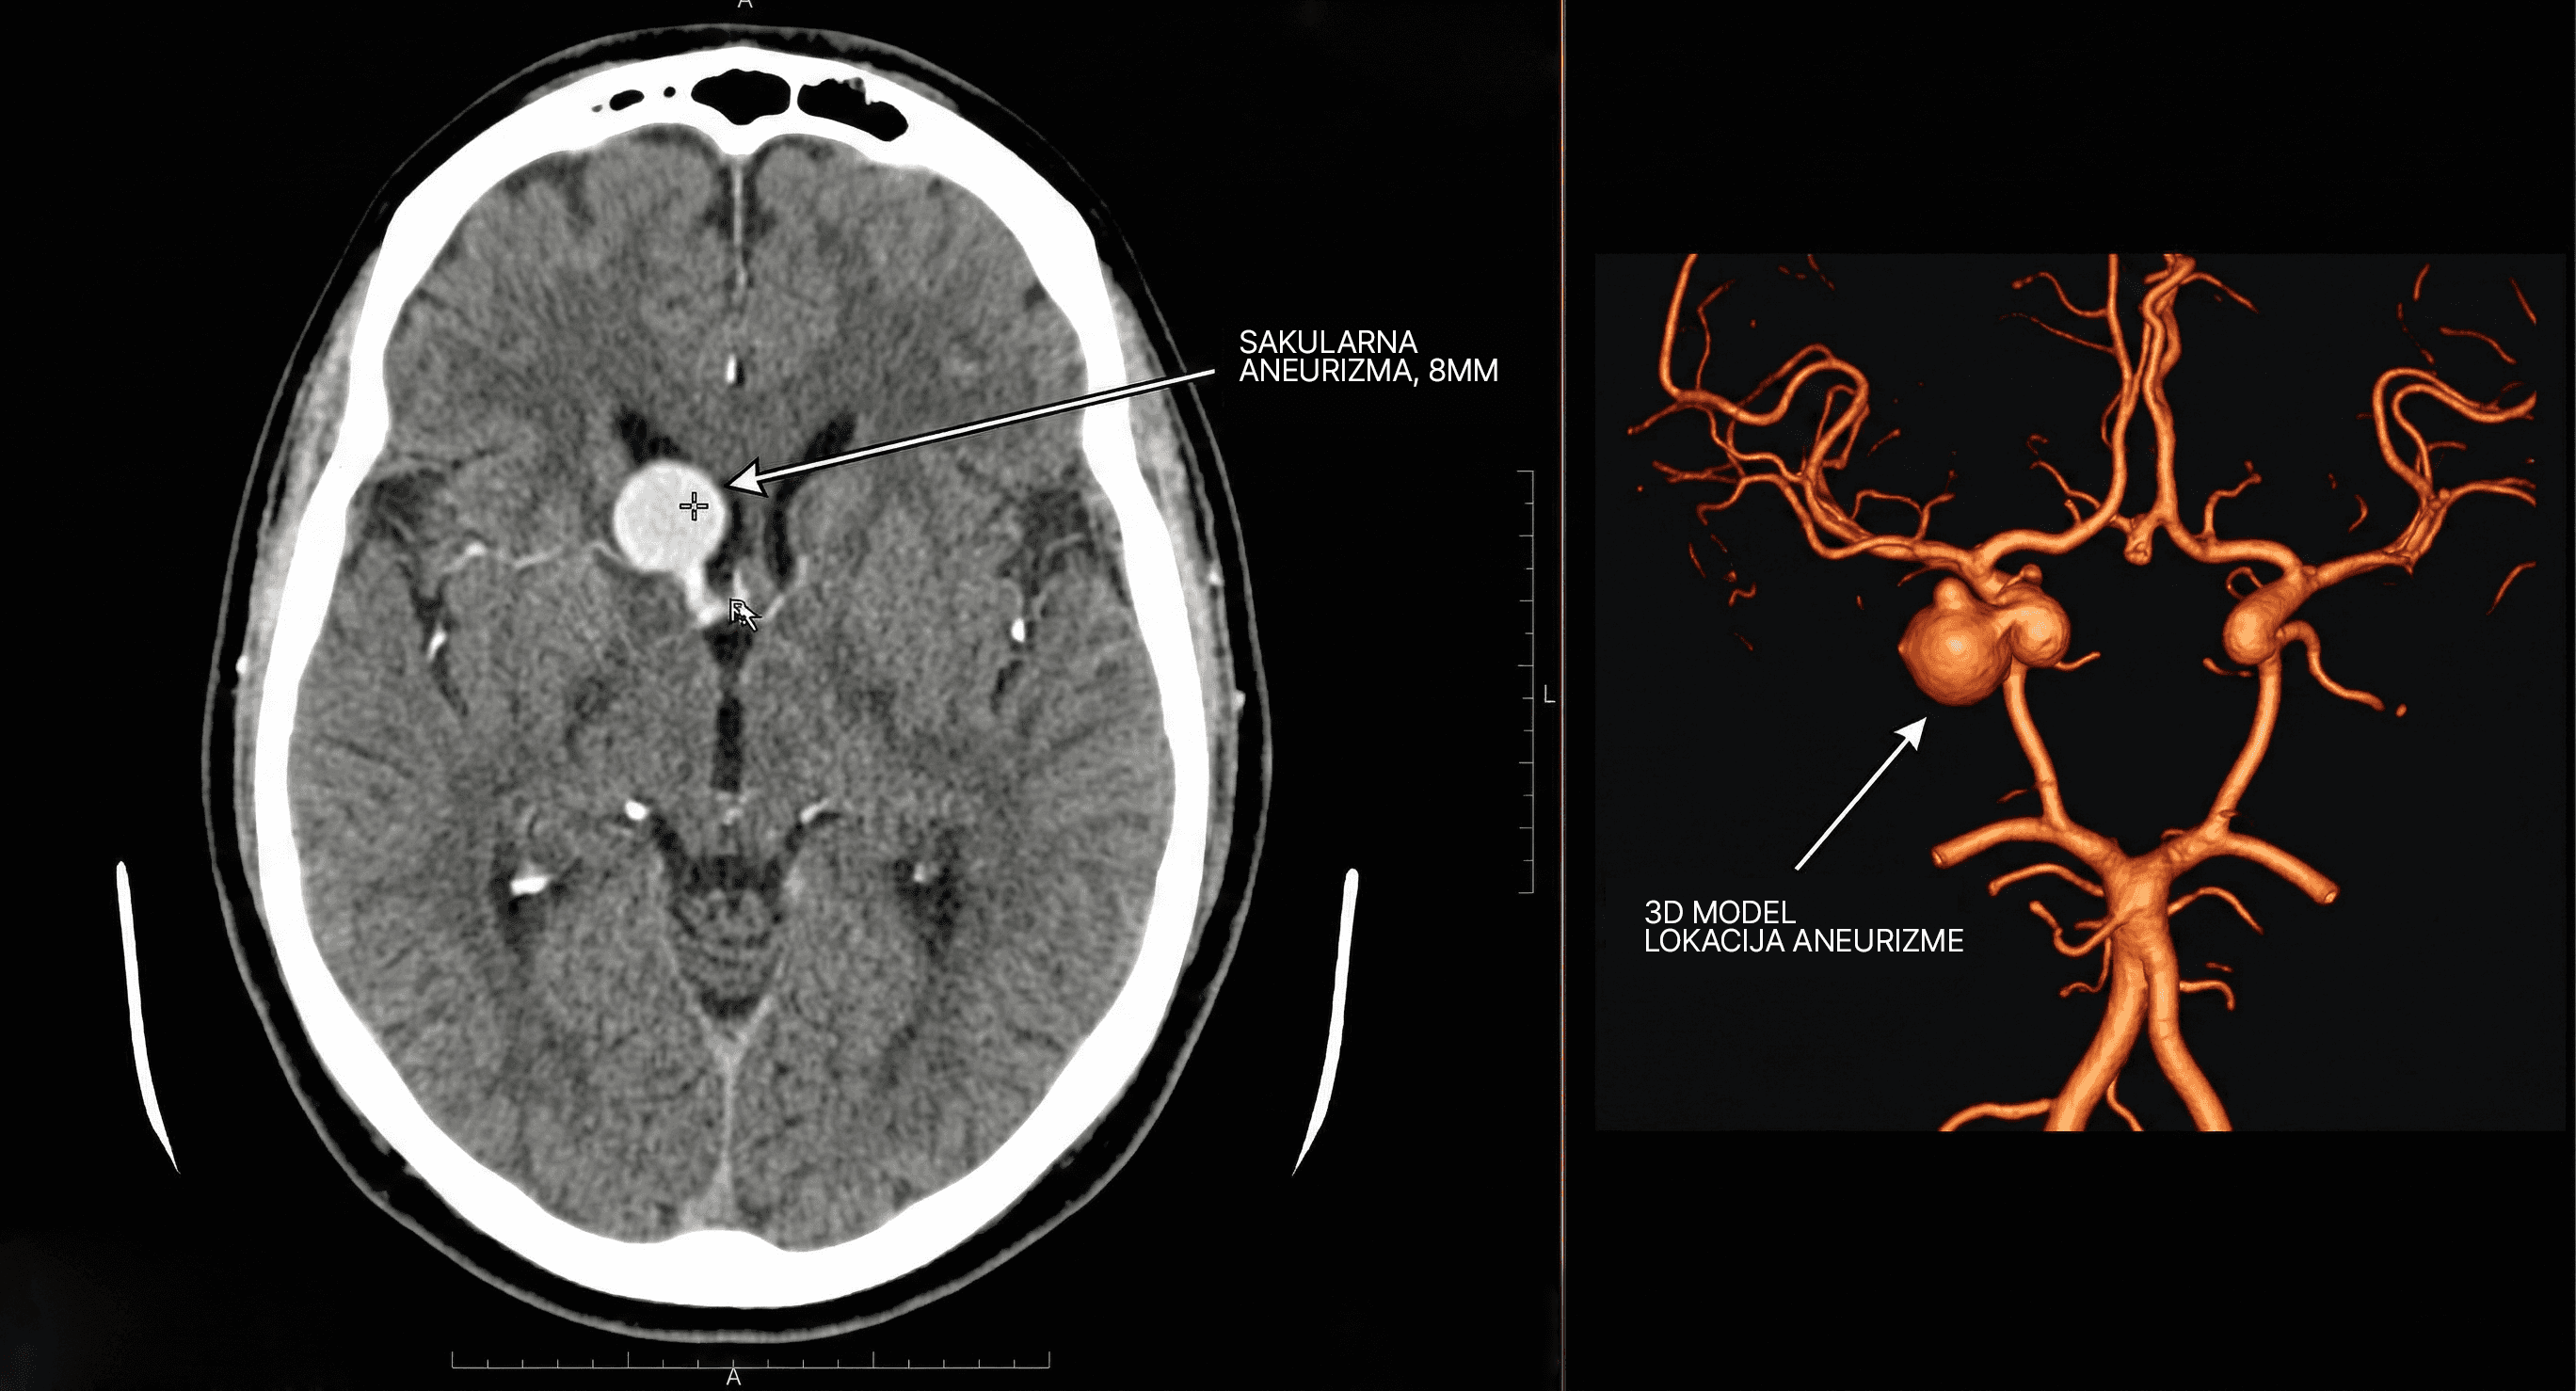

Nova Tehnologija

Nova Šansa Za Oporavak - Ako Se Reaguje Na Vreme.

Šta je mehanička trombektomija?

Minimalno invazivan postupak kojim se fizički uklanja krvni ugrušak iz arterije u mozgu.